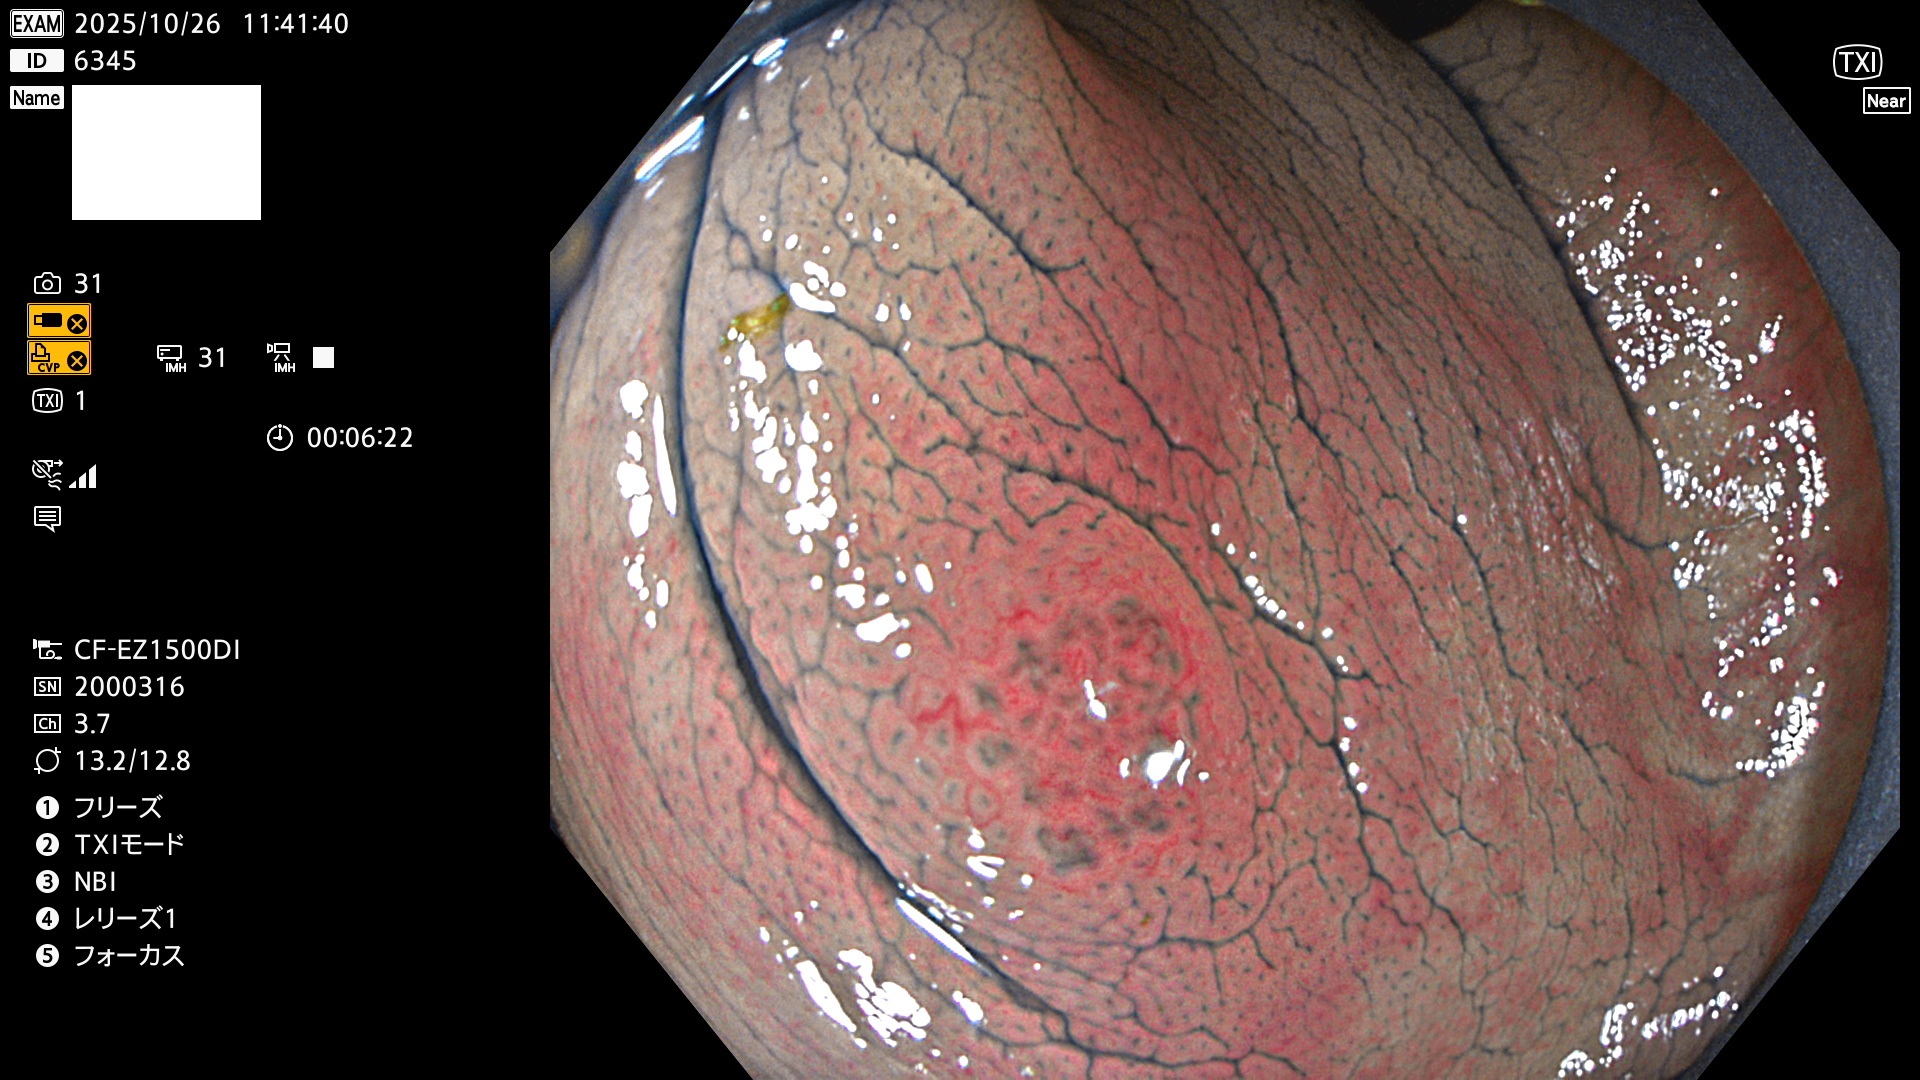

完全に平坦な物をUb、陥凹している物をUcと呼びます。Ubは認識が困難で、Ucはびらん(炎症)と紛らわしいために見落とされやすく、「内視鏡後・大腸癌」の原因になります。

毎週の検査(木・金・土・日)に発見されたUbとUc型・腺腫を、その週の日曜の夜にUPし1週間、提示します。

2025年10月23日〜10月26日の4日間(40件)6個 (Uc_ADR=6個/40人=15%)